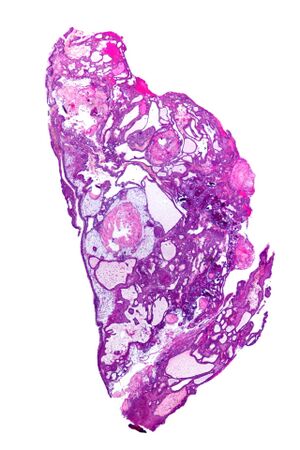

Adamantinomatous craniopharyngioma - very low mag.jpg

Very low magnification micrograph of an adamantinomatous craniopharyngioma. HPS stain.